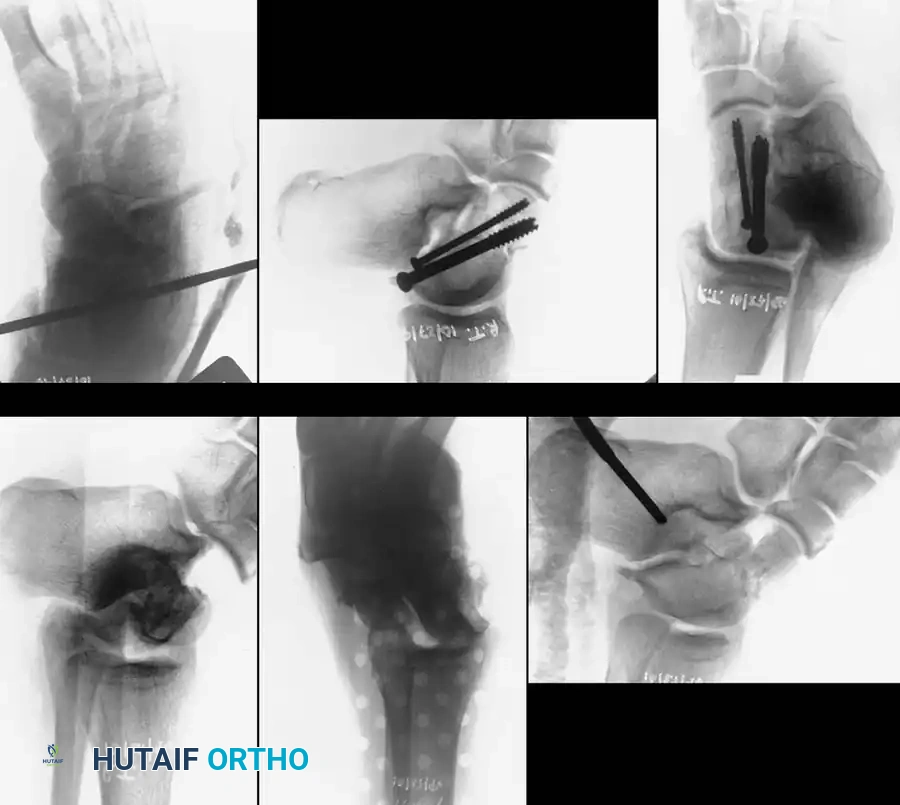

Fixation X-ray 1

Fixation X-ray 2

Posterior-to-anterior screw placement (via a posterolateral approach) is biomechanically superior as it engages the denser bone of the talar head, but it requires careful avoidance of the flexor hallucis longus (FHL) and the neurovascular bundle.

Post-op fixation 1

Post-op fixation 2

In cases of severe medial comminution, a mini-fragment plate (e.g., 2.0 mm or 2.4 mm) may be applied to the medial talar neck to act as a buttress and maintain length, preventing varus collapse.

Post-op fixation 3

Fixation X-ray 5

Fixation X-ray 6

Fixation X-ray 7